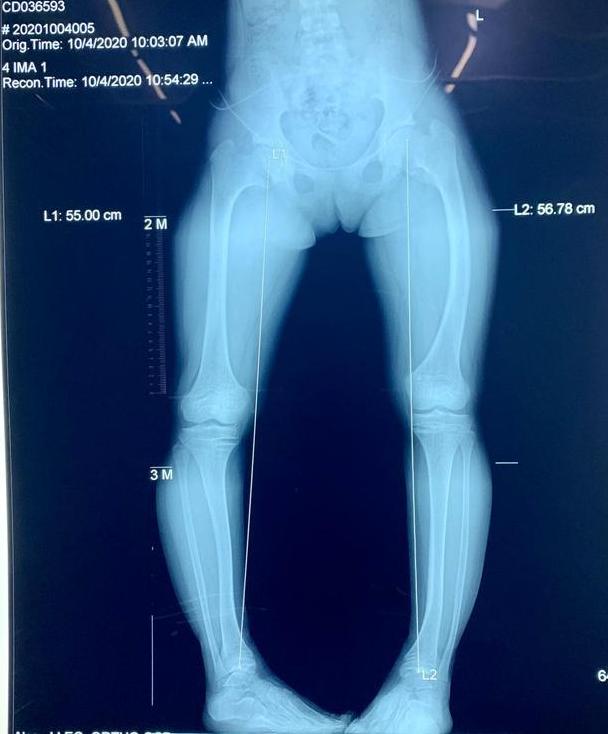

双下肢不等长的X光片

儿童双下肢不等长是小儿骨科常见的类型。原因有:外伤后骨骺异常发育、先天性双下肢发育异常、脊髓灰质炎后遗症、先天性髋关节发育异常等等。主要判断标准是影像学诊断中下肢骨骼出现绝对差值。